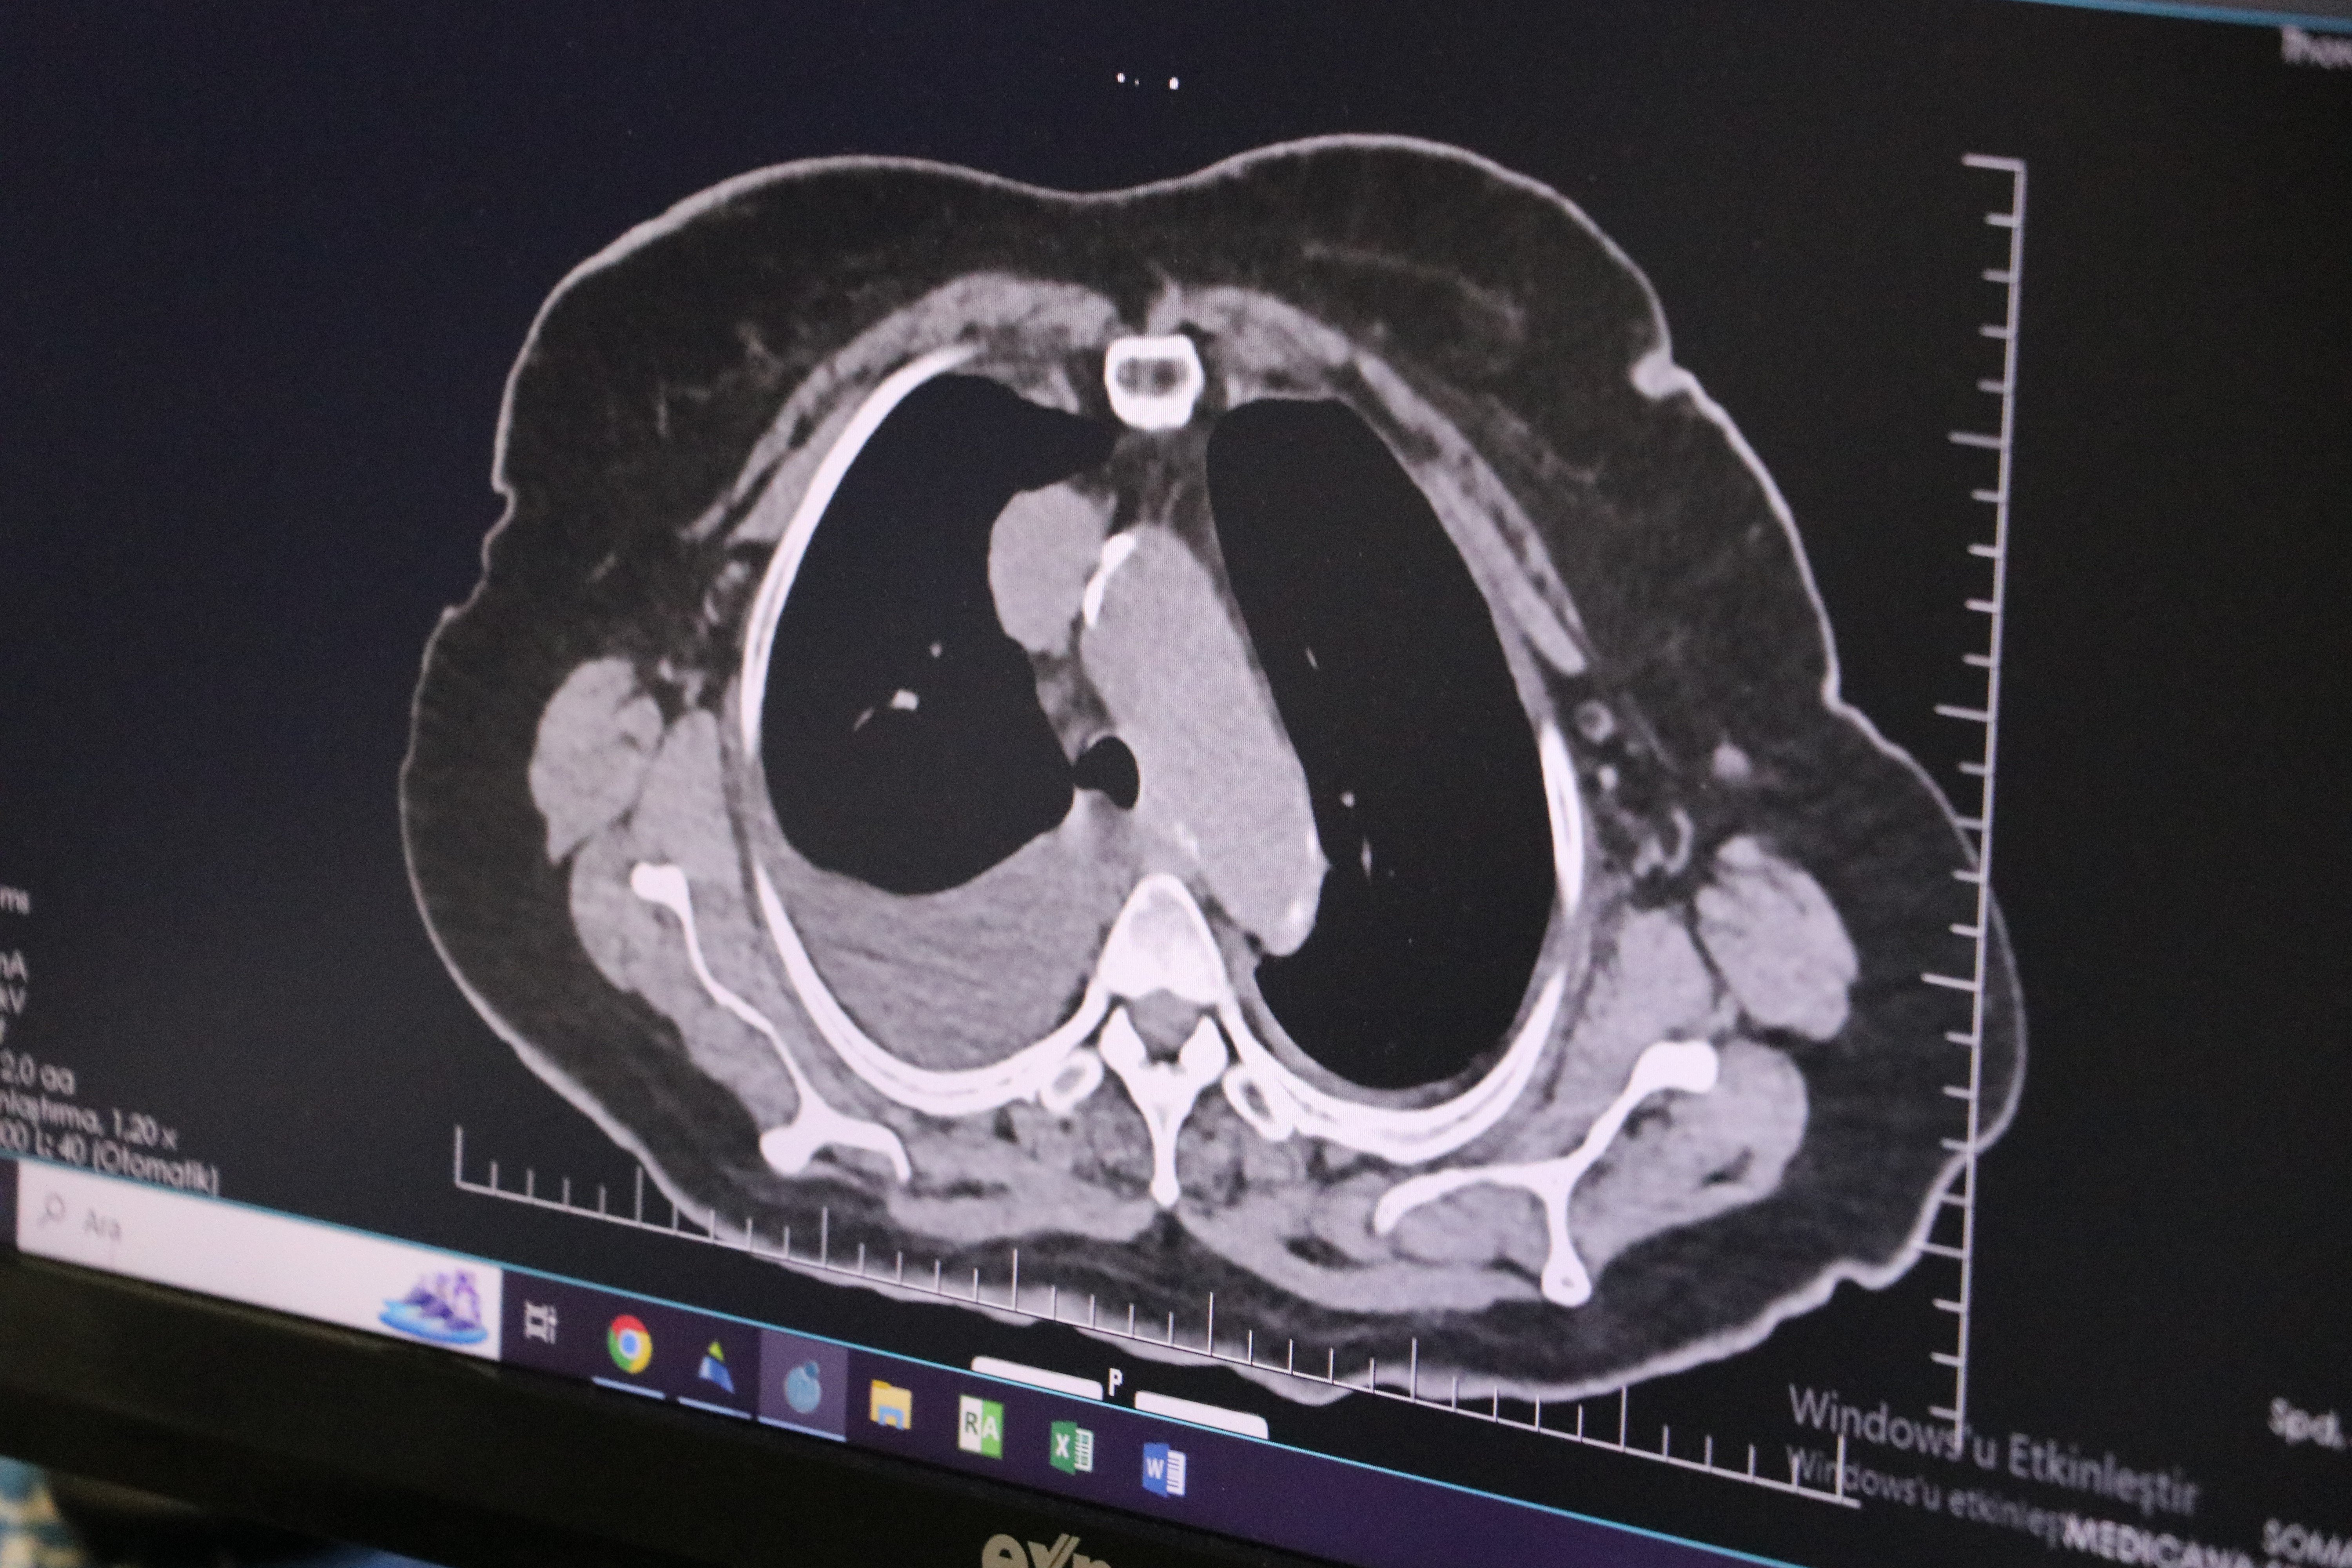

Haber görseli